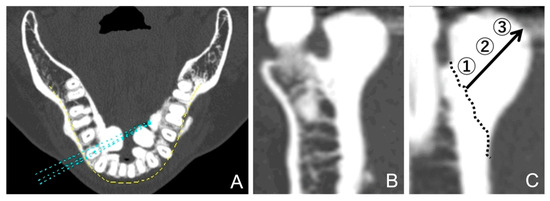

2.2. Classification of Morphology and Size

2.3. Bone Density Assessment